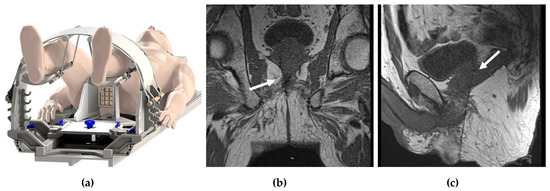

- In-Bore Transperineal: Patients are usually placed supine with legs in an MRI-compatible stirrups device. A localizer grid is placed and secured at the perineum. The reservoir of the marking block is usually filled with water. T2W images are then obtained. The point of insertion in the marking block and the depth of the target lesion are then calculated, either using available software or manually. The marking block can be left in place during the entire procedure, but some institutions remove it after identifying the skin entry site [14]. The lack of the mark block allows for fine adjustments to the needle path if needed. Images are obtained as the needle is advanced into the target, while making adjustments as needed (Figure 1).